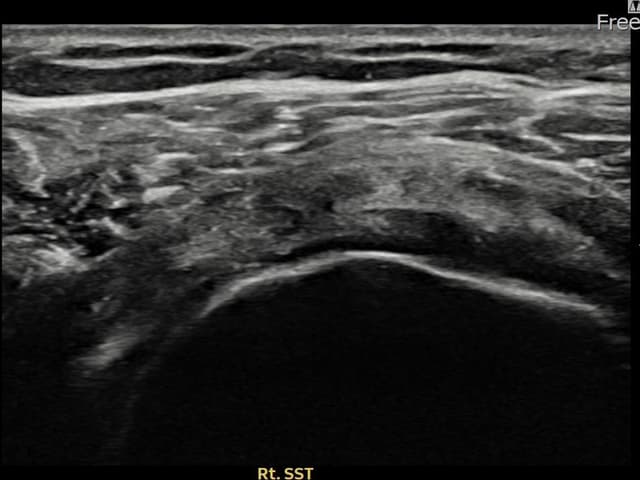

右侧 冈上肌腱 石灰化肌腱炎

14mm × 10mm